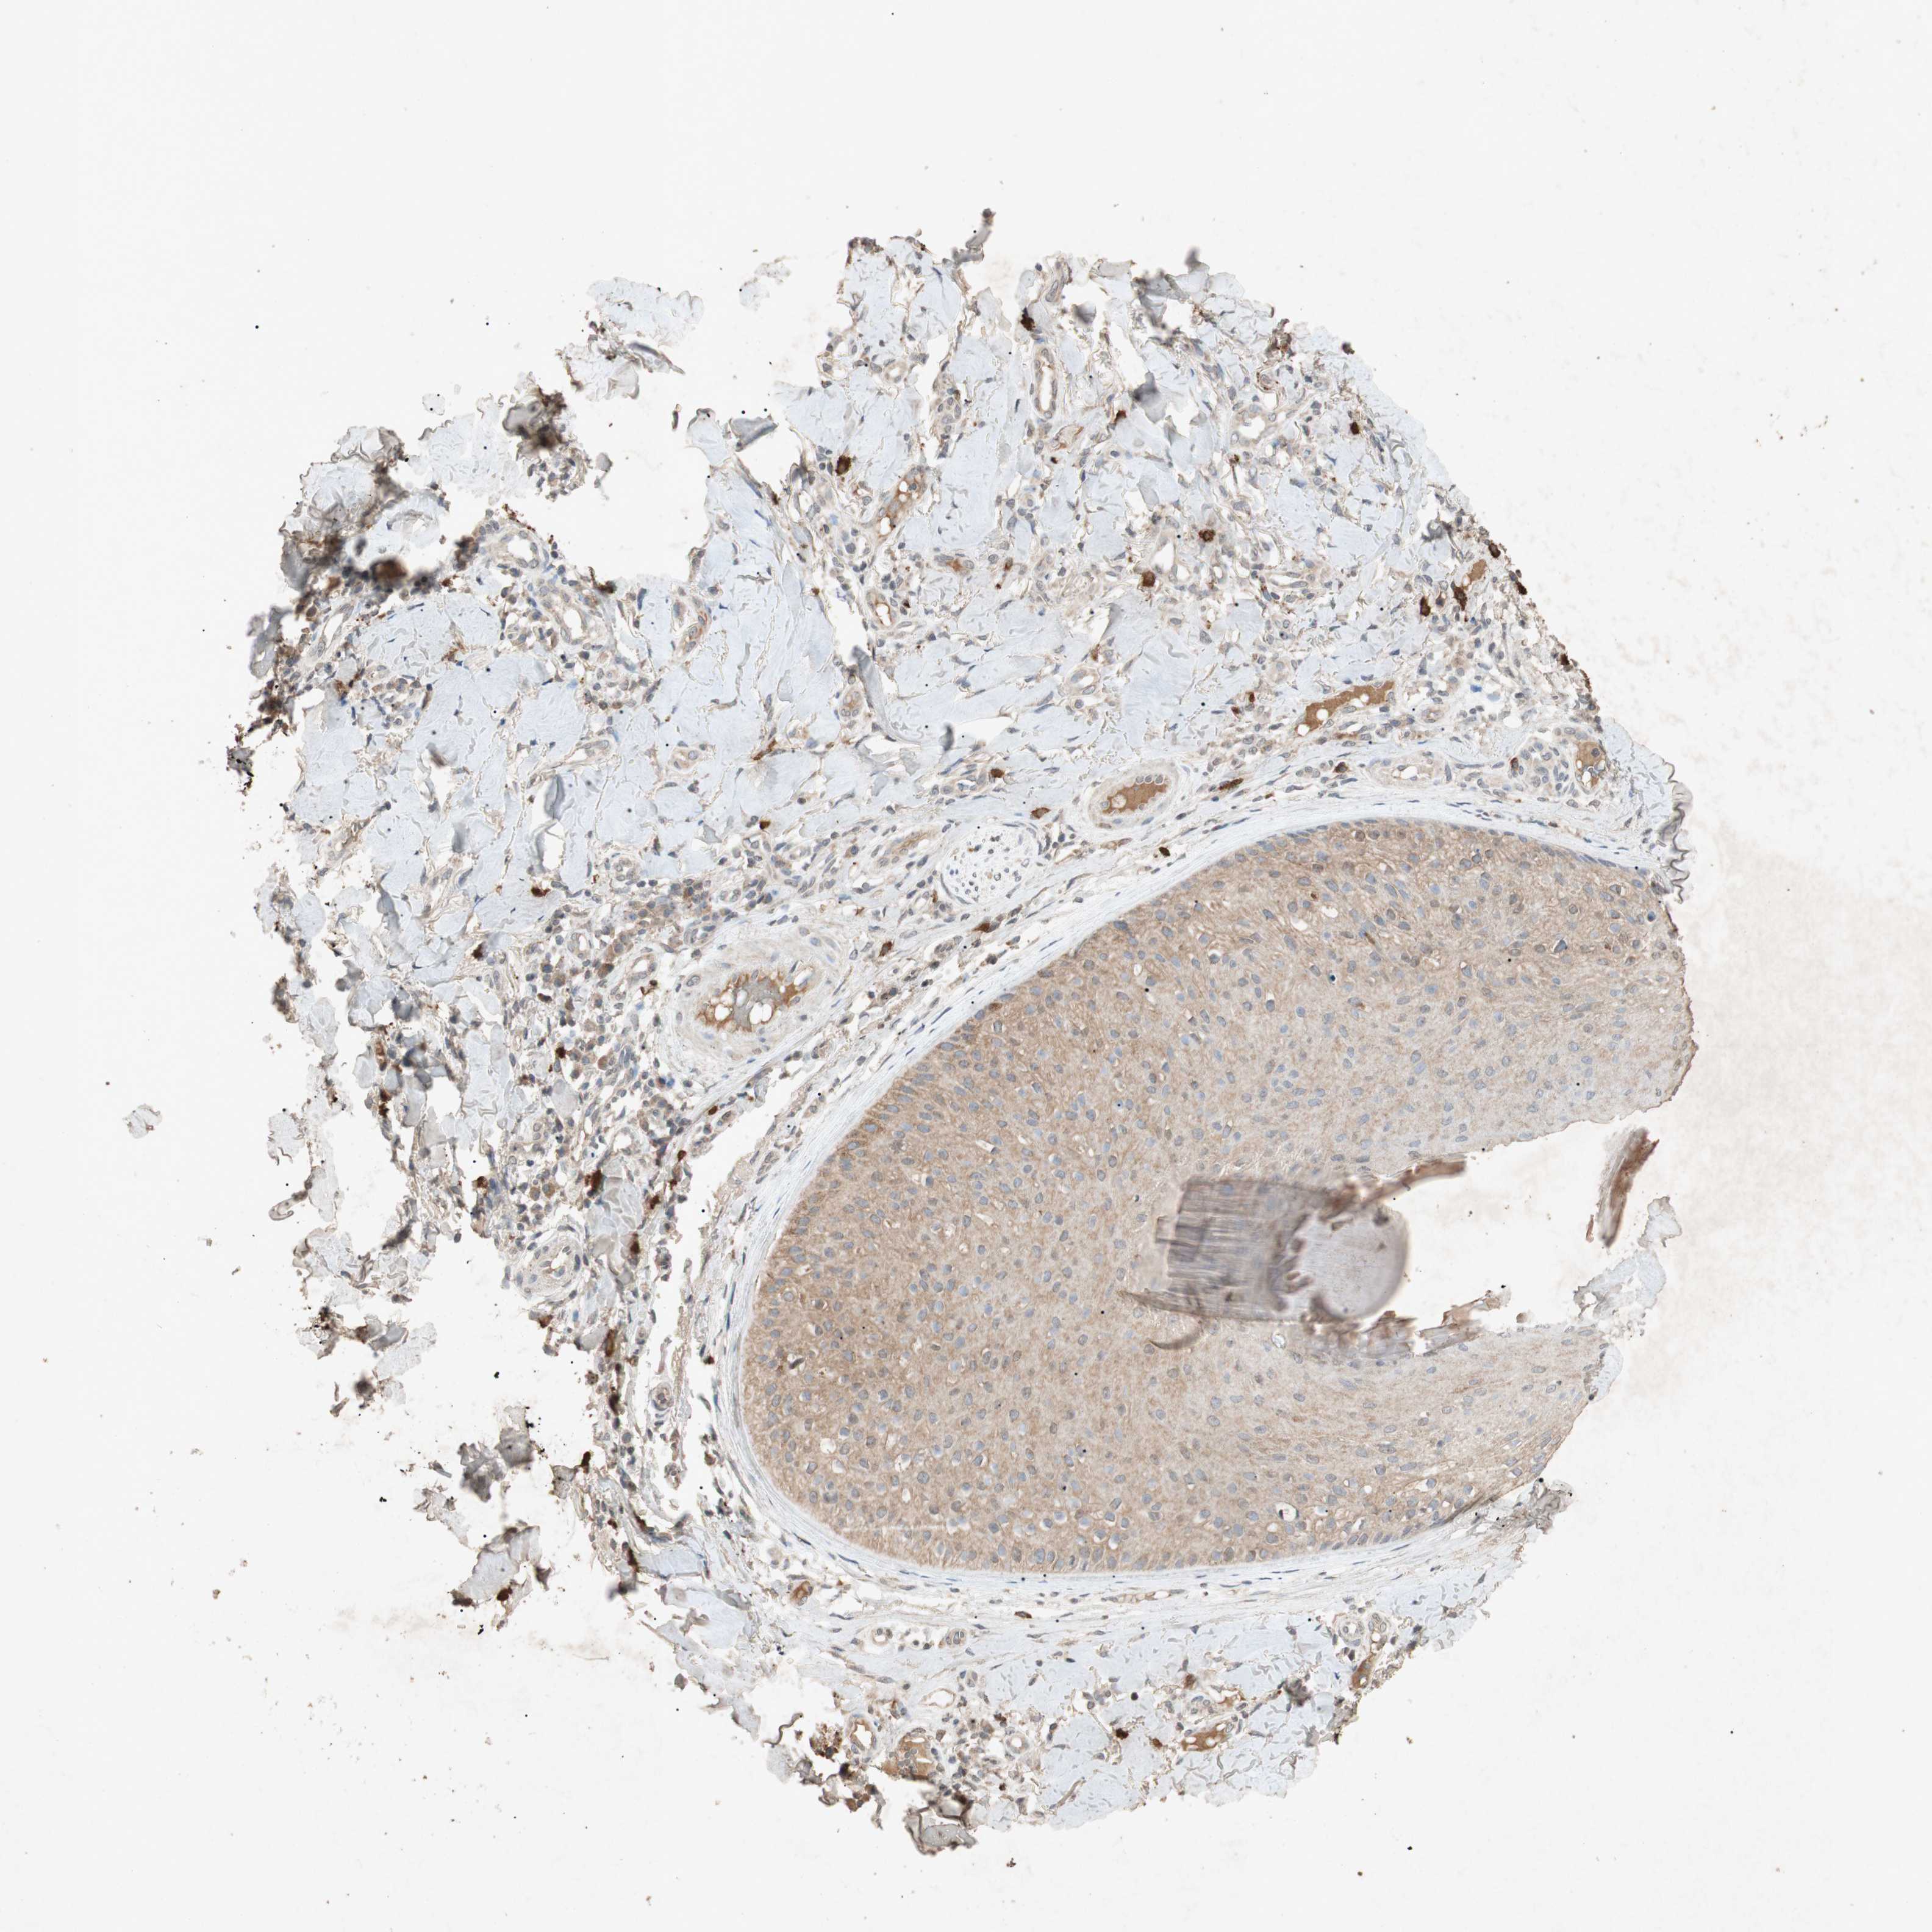

SKIN CANCER - Protein expressioni

A mouse-over function shows sample information and annotation data. Click on an image to view it in a full screen mode. Samples can be filtered based on level of antibody staining by selecting one or several of the following categories: high, medium, low and not detected. The assay and annotation is described here.

Antibody stainingi

Antibody staining in the annotated cell types in the current human tissue is reported as not detected, low, medium, or high, based on conventional immunohistochemistry profiling in selected tissues. This score is based on the combination of the staining intensity and fraction of stained cells.

Each image is clickable and will lead to virtual microscopy that enables deeper exploration of all samples and also displays staining intensity scores, fraction scores and subcellular localization as well as patient and tissue information for each sample.

Antibody HPA069557

Antibody CAB008650

Basal cell carcinoma

Squamous cell carcinoma, NOS